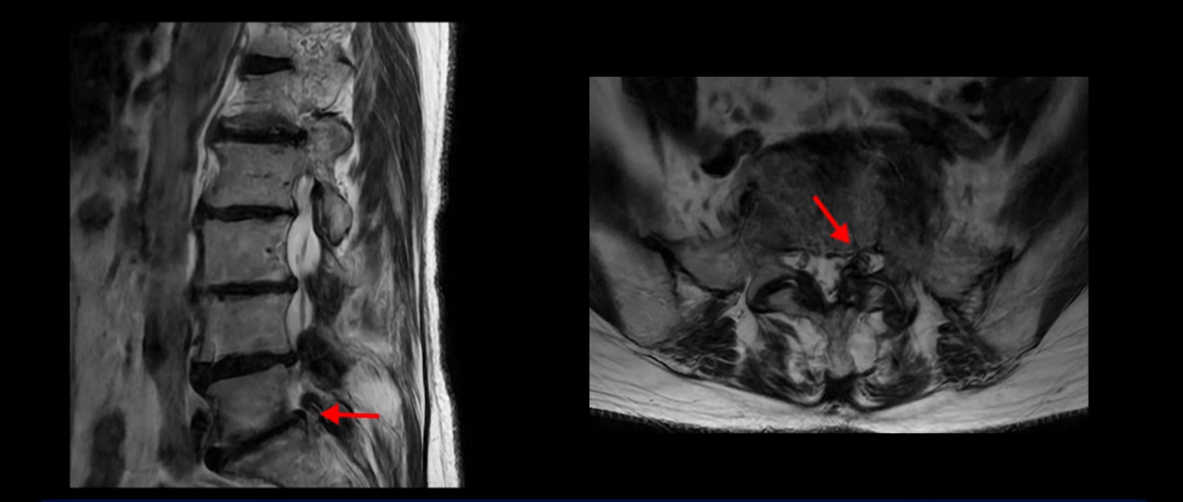

특히 4번 5번에는 심한 중심성 협착이 있고,

5번 1번에는 황색인대가 골화되어 왼쪽 신경 나가는 길이 좁아져 있습니다.

그래서 왼쪽 엉덩이와 다리 통증이 더 심합니다. 이렇게 신경 구멍들이 좁아져 있고 신경이 눌리니까 엉덩이와 다리가 너무 저리고 아프고 힘도 빠져서 몇 걸음도 걷기 어려우니까 지팡이를 짚고 저녁에도 아파서 잠을 못 자는 겁니다.